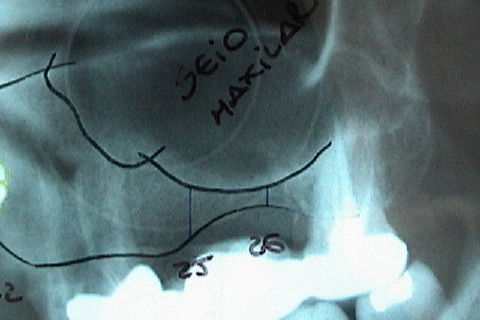

Radiografia inicial

Visáo aproximada da região a ser feita elevação do soalho do seio maxilar

Região do dente 15, onde será feita elevação do soalho do seio maxilar

Visão aproximada da área dos dentes 25 e 26, para elevação do soalho do seio maxilar